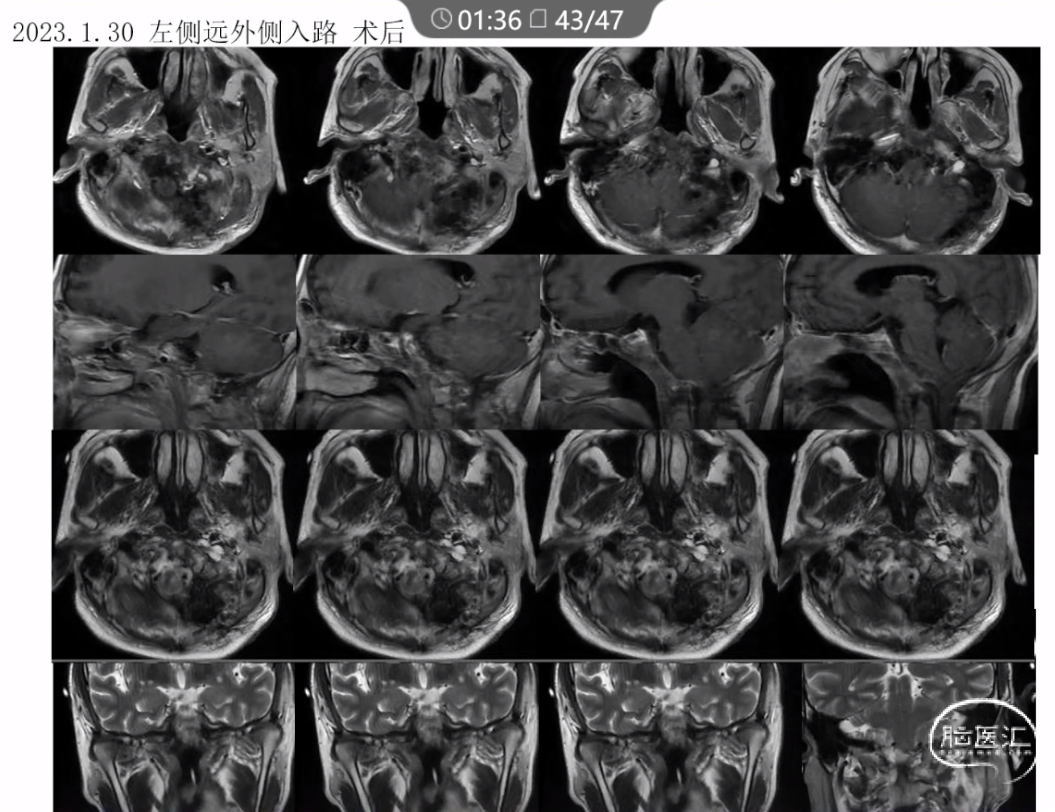

本文主要内容为:脊索瘤临床特点、治疗选择,以及多个手术病例。